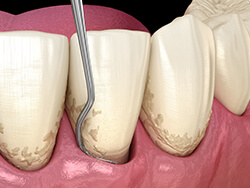

スケーリング

歯石除去

SRPとはスケーリング&ルートプレーニングの略で、 専用の器具を使用して、病原性の高い歯石を取り除く処置です。歯周病治療の1つで、ハンドスケーラーと呼ばれる専用の器具や、超音波の器具を用いて歯周ポケットの中(歯ぐきの中の歯の根に隠れている部分)の歯垢(プラーク)や歯石を取り除き、汚染された根面のセメント質や象牙質を除去してなめらかな根面にすることです。